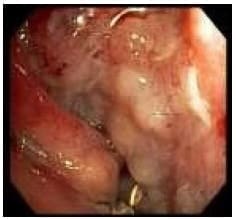

Al segundo día postquirúrgico presenta salida de material alimentario por las sondas de tórax, lo que establece presunción diagnóstica de fístula gastro-pleural, que luego se documenta por endoscopía (Figuras 1 y 2), tomografía computarizada (Figura 3) y estudio contrastado de vías digestivas altas (Figura 4).

Figura 1. Gran orificio fistuloso a la izquierda (flecha). |

Figura 2. Cavidad de la fístula abordada con el endoscopio. |